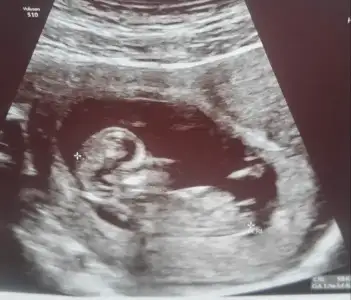

Merak etmiyordum ama siz ekledikçe heveslendim. Ben de 12. hafta resmini ekliyorum, cinsiyet yorumunuzu bekliyorum kızlar :)

Eklentiler

• 12.webp

12.webp

21,6 KB · Görüntüleme: 100

Bence kız gibi hatta geçen hafta kontrole gittik eşim heyecandan video çekmemiş bir anlık böyle bir görüntü bende gördüm dedim keşke video olsaydı tekrar tekrar bakardım. Tahmin de bulunurdum. Senin kini görünce o zaman benim kide erkek diyorum gördüğüm seninkinden farklı çünkü :))